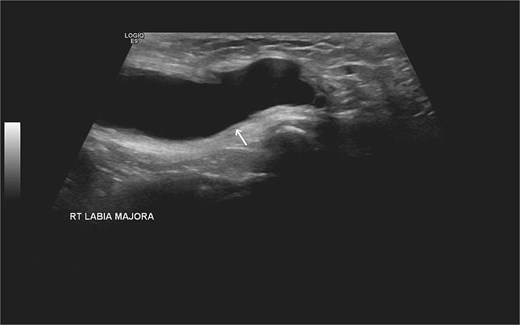

Laboratory studies, including complete blood count and comprehensive metabolic panel, were within normal limits. Initial ultrasonography (US) revealed an oblong cystic lesion with fine septations, measuring 6.5 × 3 cm, extending through the right inguinal canal into the labium majus (Figs 1 and 2). Subsequent pelvic magnetic resonance imaging (MRI) corroborated these findings, demonstrating a right lower abdominal cystic lesion with thin septations extending to the inguinal region, showing low T1 and high T2 signal intensity, measuring ~7 × 3.5 cm (Figs 3 and 4). No evidence of bowel or omental herniation was observed, suggesting canal of Nuck hydrocele.

Additional US of the right inguinal area showing fine internal septations of the lesion as indicated by the arrow.